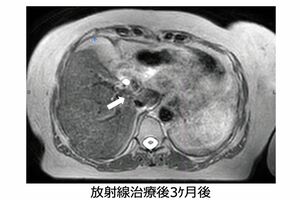

さらに、今年、最新の放射線治療が千葉大学病院に導入され、難しいとされていた膵臓がんや、肝臓がんなど、消化器に近いがんの放射線治療が可能になったという。膵臓がんといえば、5年生存率が極めて低いがんだが、最新治療によって大きく変わると期待されている。その最新治療について詳しく聞いてみた。